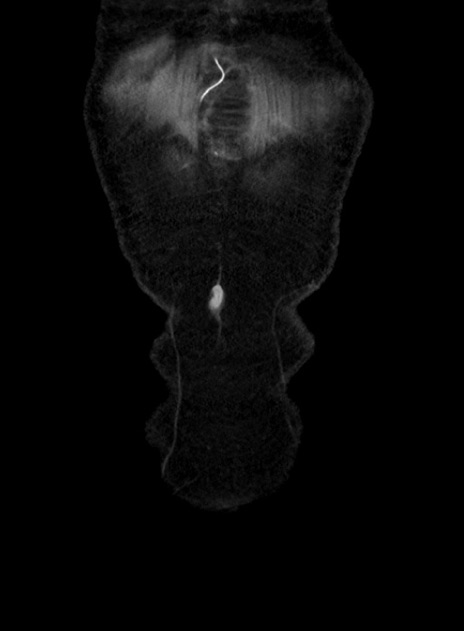

横断像